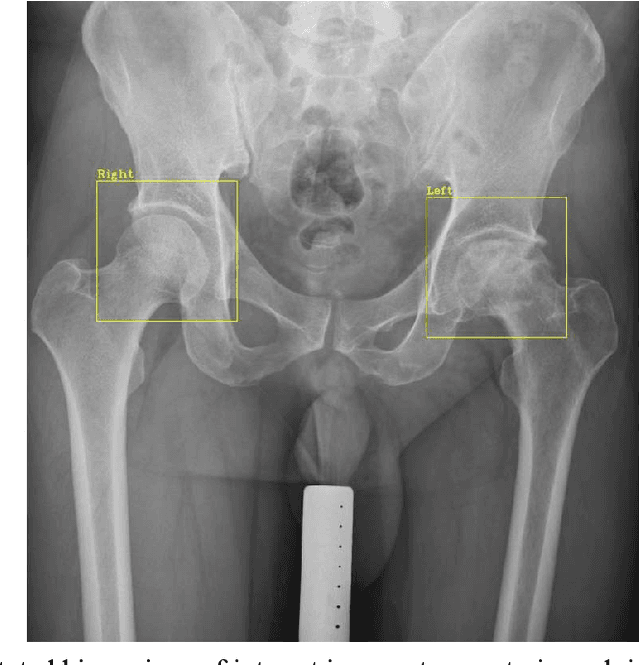

Abstract:Purpose Automated detection of region of interest (ROI) is a critical step for many medical image applications such as heart ROIs detection in perfusion MRI images, lung boundary detection in chest X-rays, and femoral head detection in pelvic radiographs. Thus, we proposed a practical framework of ROIs detection in medical images, with a case study for hip detection in anteroposterior (AP) pelvic radiographs. Materials and Methods: We conducted a retrospective study which analyzed hip joints seen on 7,399 AP pelvic radiographs from three diverse sources, including 4,290 high resolution radiographs from Chang Gung Memorial Hospital Osteoarthritis, 3,008 low to medium resolution radiographs from Osteoarthritis Initiative, and 101 heterogeneous radiographs from Google image search engine. We presented a deep learning-based ROI detection framework utilizing single-shot multi-box detector (SSD) with ResNet-101 backbone and customized head structure based on the characteristics of the obtained datasets, whose ground truths were labeled by non-medical annotators in a simple graphical interface. Results: Our method achieved average intersection over union (IoU)=0.8115, average confidence=0.9812, and average precision with threshold IoU=0.5 (AP50)=0.9901 in the independent test set, suggesting that the detected hip regions have appropriately covered main features of the hip joints. Conclusion: The proposed approach featured on low-cost labeling, data-driven model design, and heterogeneous data testing. We have demonstrated the feasibility of training a robust hip region detector for AP pelvic radiographs. This practical framework has a promising potential for a wide range of medical image applications.